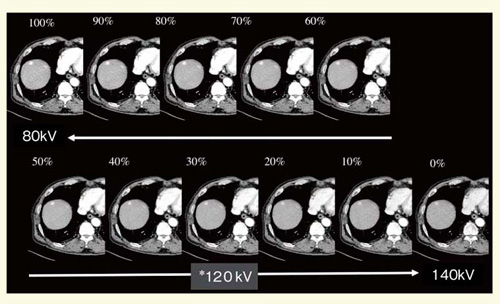

1)Composite image

80kVと140kVの画像からさまざまなcomposite imageが作成できるが,Definitionの場合は80kVを30%,140kVを70%の割合で,通常の120kVに近似した画像を作成する(図6)。SOMATOM Definition Flash(以下,Definition Flash)では,フォトンシールドをかけることによって実効エネルギーが上がるため,それぞれ50%程度に変更して120kV相当の画像を作成している。肝細胞がんのcomposite imageにおけるCNRは80kVの低管電圧の方が高く,造影剤の濃染コントラストが良くなるため,低管電圧の割合を増加させることで,腫瘍の検出率が向上する。

図6 肝細胞がんのcomposite image